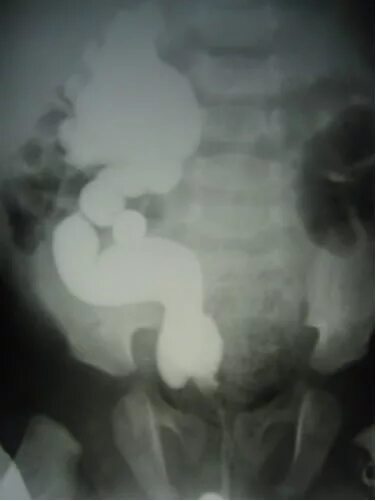

Мегауретер у детей что это